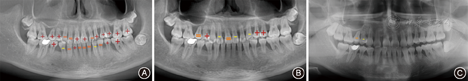

口外检查可见面部不对称和张口偏斜。口内检查可见牙龈红肿,前牙区和后牙区均存在牙齿移位和明显的牙间隙(图1)。牙周检查结果见图4A,探诊出血阳性位点达100%,探诊深度超过4 mm的位点达65%,松动牙占全口牙85%,其中Ⅲ度松动的牙齿数量达50%。影像学检查结果显示除外个别牙,余牙的牙槽骨吸收均达根长的1/3至根尖,同时发现存在右侧上颌窦炎(图5A)。应用K7咬合评估分析系统(K7 evaluation system,Myotronics-Noromed Inc,美国)检测发现患者双侧咀嚼肌电位严重不对称,下颌运动向左偏斜达17.3 mm(图6)。咬合力评估分析系统(T-scan system,Tekscan Inc,美国)显示存在早接触和

3年后随访显示,牙龈轻度红肿,病理性移位的25自动排齐,21和22以及23和24间缝隙关闭(图2)。探诊深度超过4 mm的位点百分比降至14%,Ⅲ度松动的牙齿仅占11%。影像学检查结果示牙槽骨骨量和密度均有增加,可见26、27、36近中和15、16的骨量明显增加;右侧上颌窦的炎症也得到控制(图5B)。图8示CT影像是在同一断层获取,15、16的放大影像清楚可见明显的骨量增加。8年后随访结果显示,病理性移位的牙齿未复发(图3),牙龈炎症控制良好,牙松动情况持续减轻。从2011年初始治疗至2019年,8年多来患者的牙周及整体情况显著好转;复查结果显示牙龈无明显红肿,回位牙齿维持稳定并未复发。无探诊深度超过4 mm的位点,Ⅱ度及以下松动牙齿仅占8%,无Ⅲ度松动牙齿(图4B),除15、16牙龈明显退缩,涉及退缩的还有36和24、25、26、27。影像学检查结果显示牙槽骨骨量和骨密度均进一步增加,骨白线逐渐清晰(图5C,图8)。患者对治疗结果非常满意。